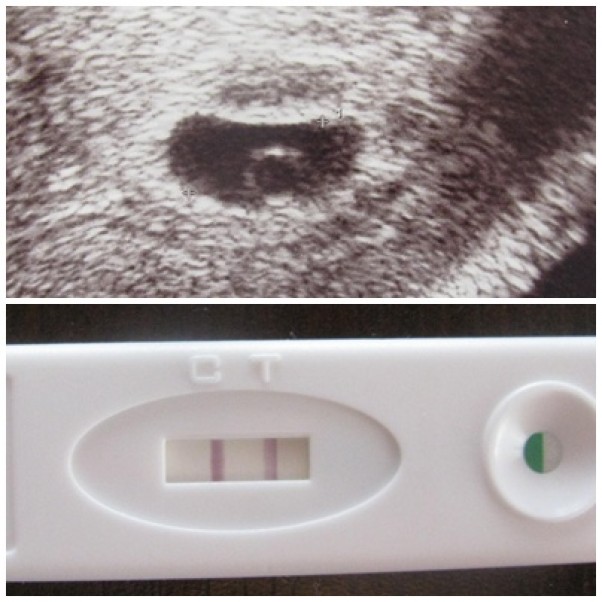

Ósmy sierpień 2014....ten dzień całkowicie zmienił moje życie. Brak okresu, 2 kreski na czterech testach ciążowych......będę mamą.